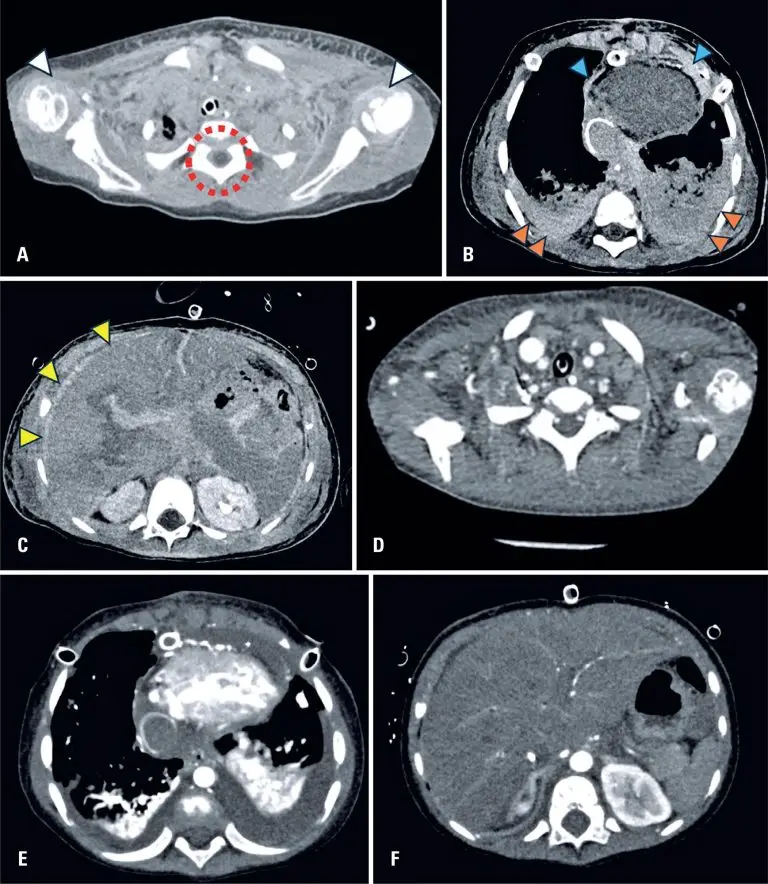

A 3-year-old boy was admitted to the hospital with decompensated congenital heart disease, hypotension (serum lactate: 100mg/dL), and acute renal failure (serum creatinine: 3.54mg/dL). Hemodynamic angiography was performed to assess cardiac pressures with a volume of 120 mL at a rate of 15 mL/s of iodinated contrast. Approximately 4 h later, the patient underwent a chest computed tomography (CT) scan using a 320-section scanner without intravenous injection of iodinated contrast or use of general anesthesia. Vicariant contrast excretion was observed in virtually all the body tissues (). Ten days later, after further evaluation using chest CT, these findings were no longer observed ().